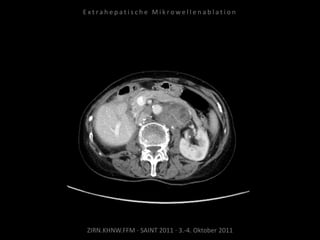

Ausgangsbildgebung:

CT vom 16.08.2010

Verlaufskontrolle:

CT 13.12.2010